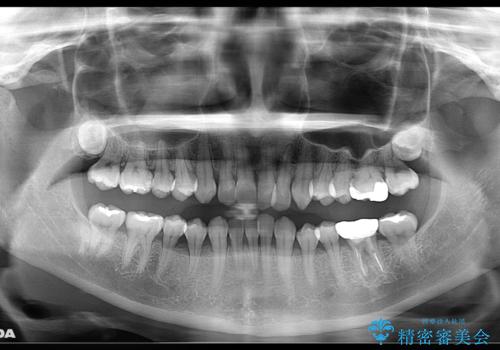

- 元々は矯正治療を主訴にご来院されました。

治療を始めるにあたり、精密検査を受けていただき全体の状況を把握したうえで矯正治療の計画を立てることとなりました。

その過程で左下の6番目の歯は治療が必要な状態であることが分かり、被せ物を外して内部を確認してみると根が破折してしまっていることが判明しました。

歯が深い位置で破折している場合は基本的には抜歯が選択されます。

様々な治療プランを患者さんと相談させて頂き、最終的にインプラントで噛み合わせを回復させていくこととなり、まず悪くなっている歯を抜歯することから開始しました。

当院では矯正治療を主訴にご来院された方は治療開始前に必ず精密検査を受けていただきます。

ご本人は症状もなくご自覚がなくても実は歯周病が進行していたり、根管治療が必要な歯が見つかるということもあります。

基本的にはそういった歯周病・虫歯に対しての治療は矯正治療開始前に完治させておく必要があります。これは、矯正装置装着後は清掃不良になりやすく虫歯の進行が早まったり、歯を移動させることで歯周病や根尖病巣が悪化する恐れがあるためです。